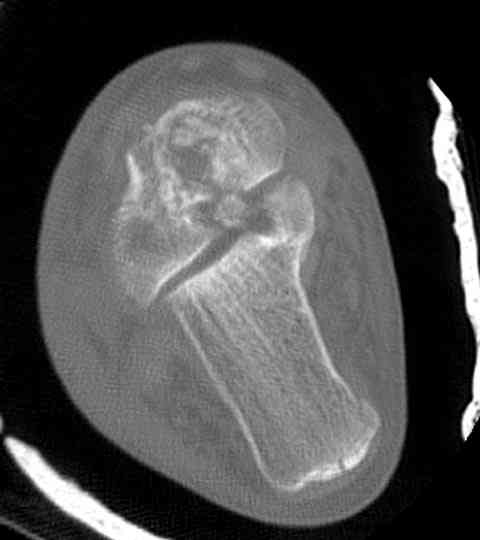

И второй случай из недавней ташкентской практики, (извините за качество ренгенограммы и только в одной проекции) случай падения с высоты (кстати моего друга - известного киноактера) - открытый

смещенный перелом тарана, с переломом переднего края дистального эпиметафиза большеберцовой кости.

При поступлении в приемной сделана первичная обработка с ушиванием открытой латеральной раны и вытяжением за пятку.

Из-за отсутствия времени пришлось оперировать на второе утро, из материала, что имеем на месте, фиксирован двумя шурупами, а третий-это контур сломанного жойстика в 4 мм. На дистальный медиальный конец тибиа antiglide 3.5 мм пластина. Через пару дней выписан и несмотря на предупреждение, самостоятельно начал нагрузку в 4 недели, время не ждет, снимается в боевике в Росийской Федерации.